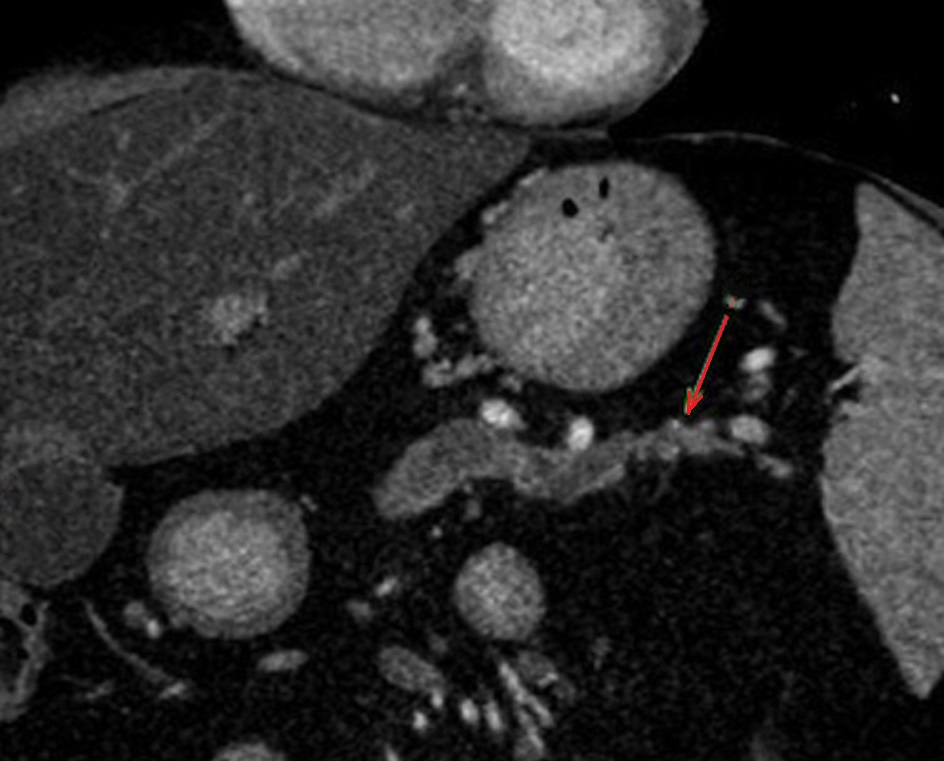

Image radiologique IRM

ponderee T1 au dessus est image d'une TIPMP de type

canaux secondaire avec aspect lesionnel des kystes

arondie , hypointense situes a la tete du

pancreas ( fleche rouge ) . Image radiologique

IRM a ponderation sur T1 , en coupe axiale |